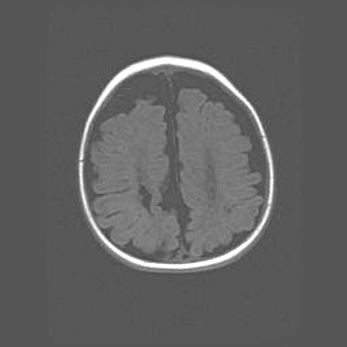

Сообщающаяся гидроцефалия. Кистозная энцефаломаляция головного мозга.

Возраст: 3 месяца 4 дня

Вес: 3100 г

Пол: женский

Окружность головы: 34 см

Срок гестации: 31 неделя

Кистозная энцефаломаляция головного мозга - одна из форм поражения головного мозга в детском возрасте. Характеризуется возникновением множественных и распространённых кист в коре, белом веществе и подкорковых образованиях головного мозга у плодов, новорождённых и детей раннего возраста. Развитие кистозной энцефаломаляции связано с внутриутробной асфиксией и гипотонией, родовой травмой, тромбозом синусов, пороками развития сосудов, инфекциями, сепсисом и другими причинами. Наиболее значимые инфекционные агенты: вирусы простого герпеса, цитомегалии, краснухи, токсоплазмы, энтеробактерии, золотистый стафилококк и другие.